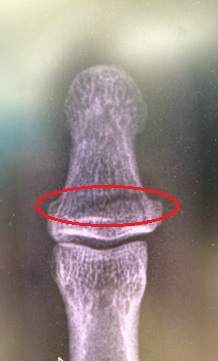

My Ironman (IM) trg has taken a bit of a hit. In a build-up half IM race I decided to trow myself off my bike but not forgetting to do my best superman impression before hitting the deck pretty hard. My initial annoyance was the damage to my bike; carbon fibre is costly! Although pretty battered, bruised and scratched (mainly to my pride), in good old Army fashion, I soldiered on finishing the remaining 20km of the bike leg and the 21km run. Post-race clean-up and a trip to A&E the next day confirmed I had actually broken my thumb; I did feel a fair amount of pain whilst trying to change gear – now I know why.

What impressed me most during my treatment was the thermoplastic thumb splint (available in a choice of colours) complete with water friendly Velcro securing strap, although I’ve already got some design mods in mind for version two. It means I can still compete in my next half IM trg race in 2 weeks’ time before the thumb is estimated to be fully healed 6 weeks from now.

Below are some pics…